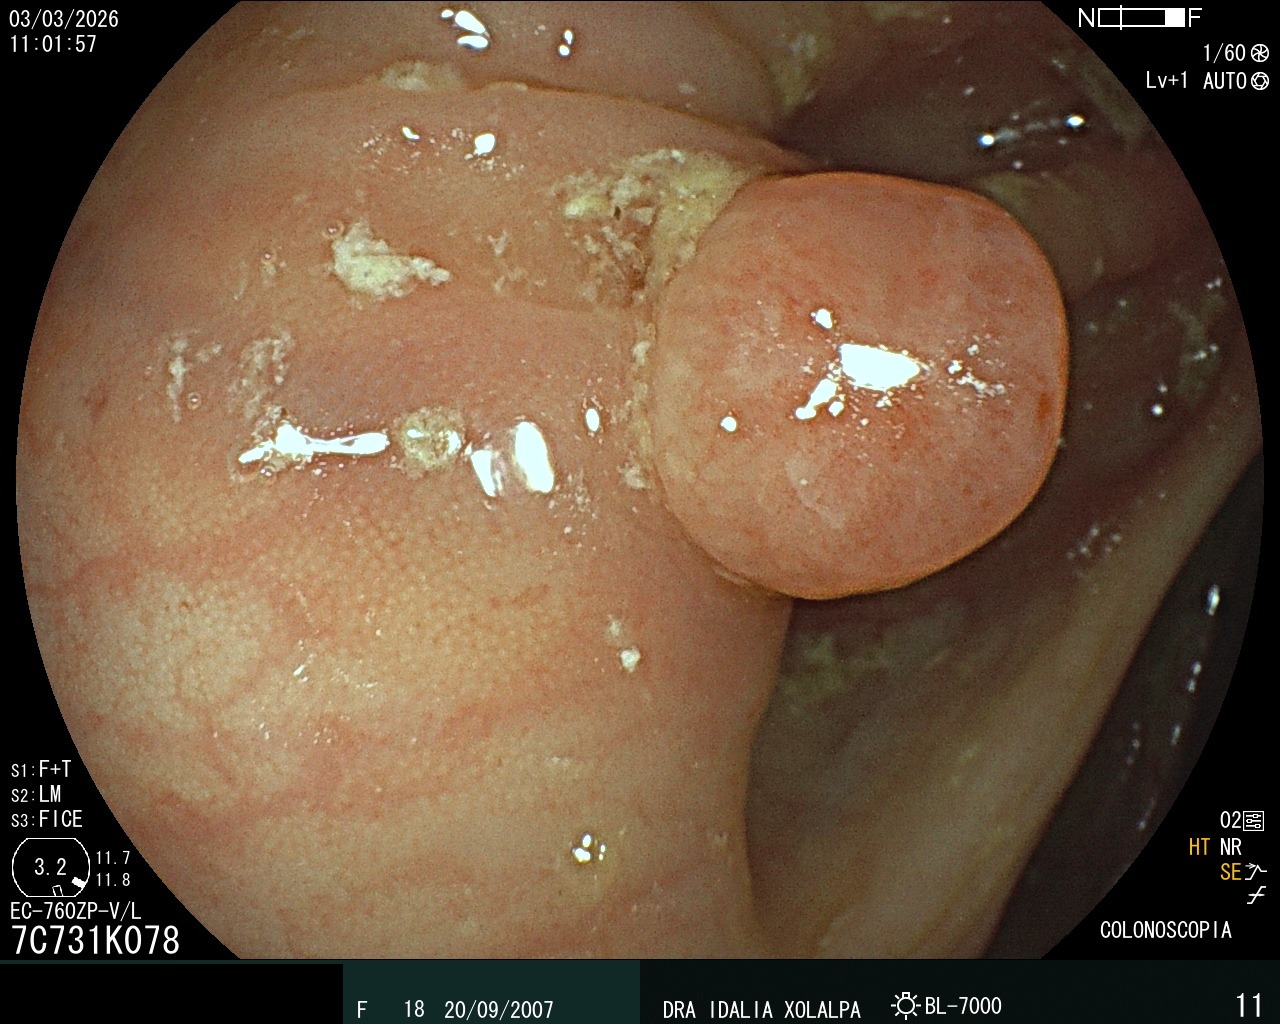

Pólipo de Colon